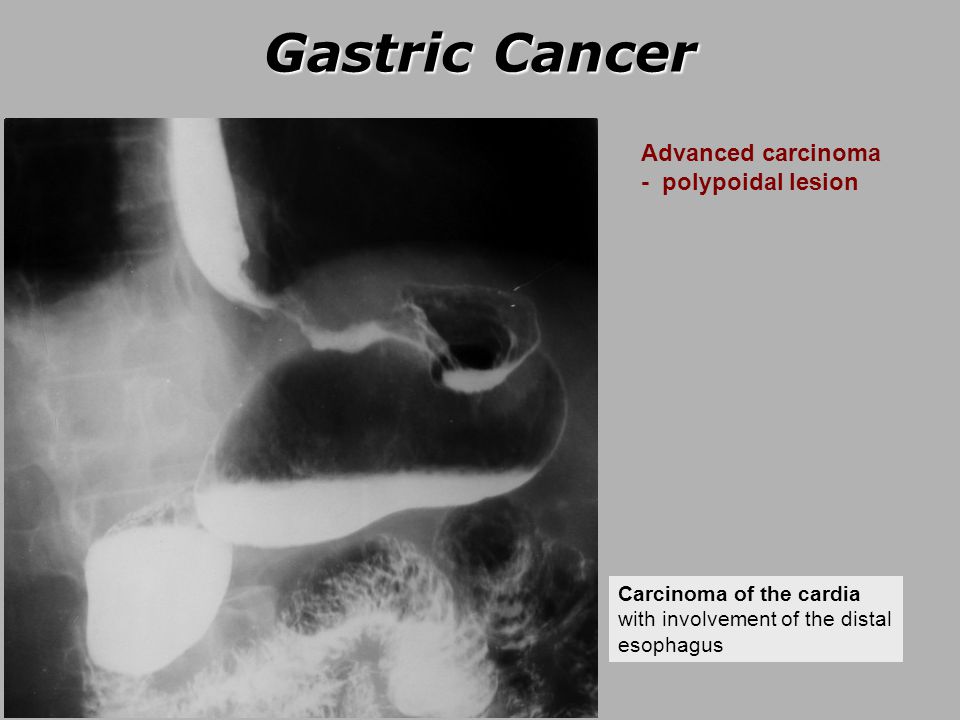

Gastric cardia radiology. Diagnostic centers of america dca is a leading diagnostic imaging facility offering a full array of imaging services in palm beach county florida. We have five state of the art radiology imaging centers in boca raton boynton beach delray beach and wellington florida. The gastric cardia is characterized on barium stud ies by three or four stellate folds that radiate to a central point at the gastro esophageal junction also known as the cardiac rosette fig 2 12. Variations and benign influences may closely resemble the more dangerous lesion.

Thick tortuous folds or lobulated filling defects in the cardia or fundus. Right gastroepiploic artery inferiorly and left gastroepiploic artery and short gastric arteries superiorly fundus of the stomach. Results of surgical treatment of carcinoma of the esophagus and gastric cardia. The collection of cases presented here comprises only that material which is rare in our experience or quite new to us.

A healthier weight from surgery can help improve or resolve many obesity related conditions such as type 2 diabetes high blood pressure joint pain heart disease and more. Medically treated small gastric ulcer. Left and right gastric veins drain to portal vein. Ugis has a 70 90 detection rate.